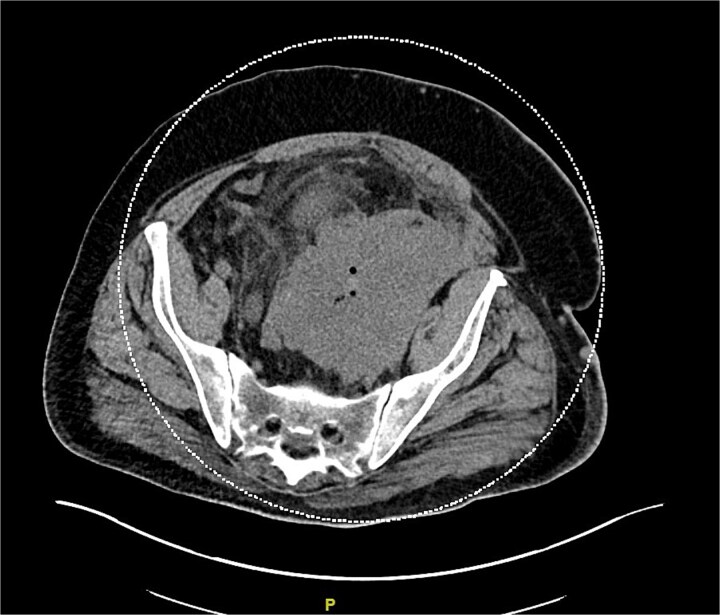

默克尔细胞癌(MCC)是一种罕见的侵袭性神经内分泌恶性肿瘤,通常出现在皮肤,并迅速进展到其他身体部位。MCC通常出现在阳光照射的区域,主要是头颈部以及上肢和肩部。它通常影响皮肤白皙的老年男性。在这个报告中,我们提出一个不寻常的MCC病例,一个48岁的白人男性,最初的表现是一个巨大的肺栓塞。患者的进一步检查显示没有典型的MCC皮肤表现,而是疾病转移。本报告的目的是强调即使患者没有常见的MCC危险因素或皮肤表现,也应将MCC视为鉴别的重要性。

Merkel cell carcinoma (MCC) is a rare aggressive neuroendocrine malignancy that typically presents in the skin and rapidly progresses to other body parts. MCC is typically found in sun-exposed areas, mainly the head and neck region as well as the upper limbs and shoulders. It typically affects fair-skinned elderly males. In this report, we present an unusual MCC case of a 48-year-old Caucasian male with an initial presentation of a massive pulmonary embolism. Further work-up of our patient indicated no typical MCC skin presentation, but rather metastases of the disease. The goal of this report is to highlight the importance of considering MCC as a differential even when patients do not present with common MCC risk factors or skin presentations.